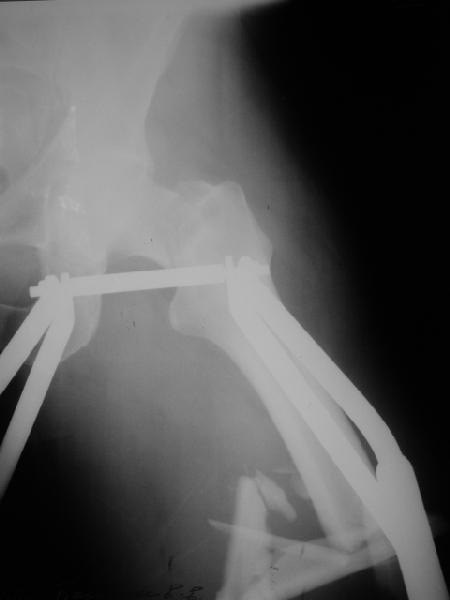

В продожение предшествующего обсуждения. В ущерб академизму для уменьшения объема кладу только одну проекцию, суть проблемы из нее ясна.

У больного 51 года в результате автоаварии 2 нед. назад перелом шейки бедра (как обычно в таких случаях, вертикальный) и открытый (прокол изнутри, ушитая по месту первичного поступления рана 2 см) многооскольчатый перелом диафиза этого же бедра. Видимо, тоже такой перелом надо кодировать как два отдельных, с плюсом, по совету проф. Лазарева?

Как лучше оперировать? От доступных вариантов глаза разбегаются - антеградный диафизарный гвоздь плюс винты в шейку бедра мимо гвоздя, реконструкционный с винтами в шейку сквозь гвоздь, гамма или проксимальный гвоздь аналогично, винты в шейку плюс гвоздь через колено; пластины и аппараты тоже доступны. На чем бы Вы остановиливыбор и почему?

Recently I posted an image of ipsilateral trochanteric and spiral shaft fractures, with request to pick a most appropriate code for the injury using AO/OTA fracture classification. I receive a couple of replies from Russian ortho list with advice to code fractures separately maybe adding '+' sign. Is this approach common? Or there is another opinion about proper coding?Now same question is about ipsilateral neck and shaft fractures. A male 51 years old referred to our unit 2 weeks after a car accident with the injury. What is correct OTA/AO code for this?The shaft part was open - a puncture wound, no signs of infection. Also the patient has a right forearm fracture - both shafts, and left clavicula.There is a lot of treatment options available for the femur - antegrade shaft nail and neck screws "miss a nail", reconstruction, gamma or proximal nails, a retrograde nail and screws to the neck; plates and external fixators are also available. What and why would be best choice?